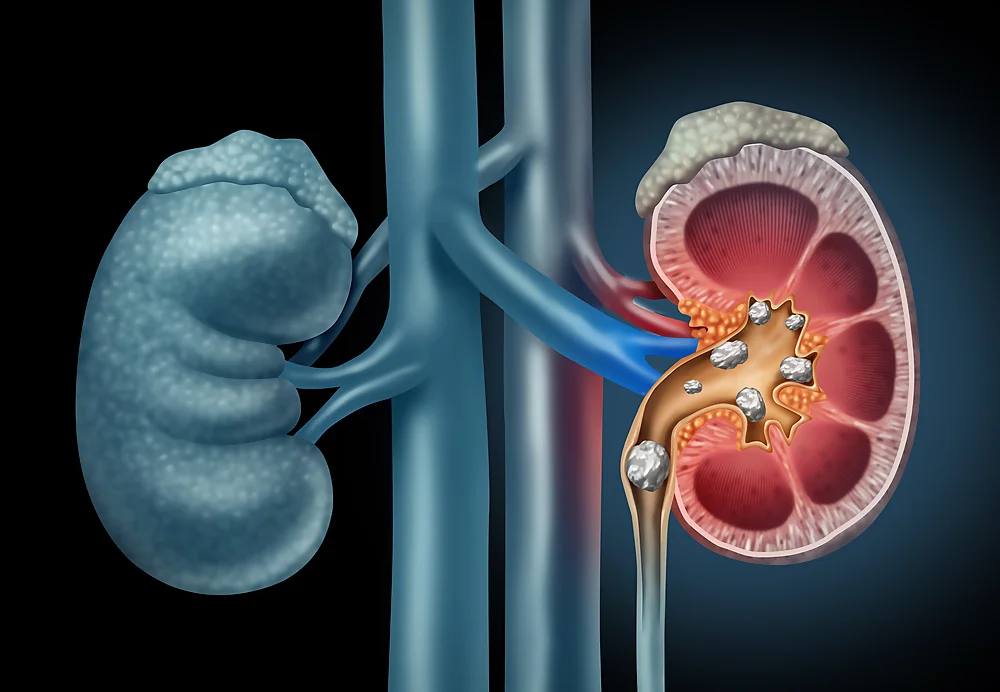

- Kidney Stones • Georgetown • Naturopath • Natural Health Clinic of Halton (March 19, 2017)

- Kidneys, Genitourinary/Renal System Conditions • Georgetown • Naturopath • Natural Health Clinic of Halton (March 19, 2017)

- Glomerulonephritis • Georgetown • Naturopath • Natural Health Clinic of Halton (March 19, 2017)